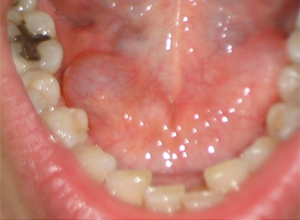

• Mucocele de labio inferior

Mucocele de Glándula Sublingual

Mucoceles

Es la acumulación de saliva dentro de una cavidad quística.

Hay dos tipos de mucocele de extravasación y de retención.

El 70% de los quistes de extravasación se observan en el labio inferior.

Los mucoceles del piso de la boca, que son más grandes, a menudo se denominan ránulas.